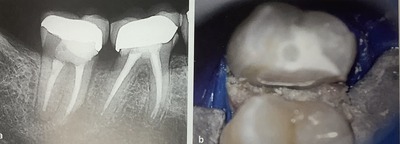

左のレントゲンでは、

外側に真っ白に見える被せ物が中身を十分にはおおっていないように?見えます。

歯の間が深くて骨に近いです。

左の写真では、コアが真っ白なんでどこまでおおうべきなのか?が分かりやすいですね。

青いラバーが歯ぐきを押し下げてくれ、顕微鏡で明るく大きく見えますから。